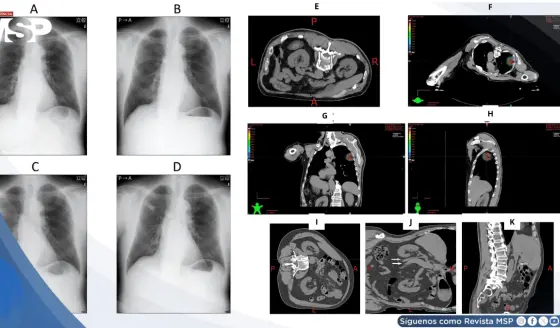

Náuseas y sudoración súbita durante radioterapia resultó en compresión idiopática de vena cava inferior